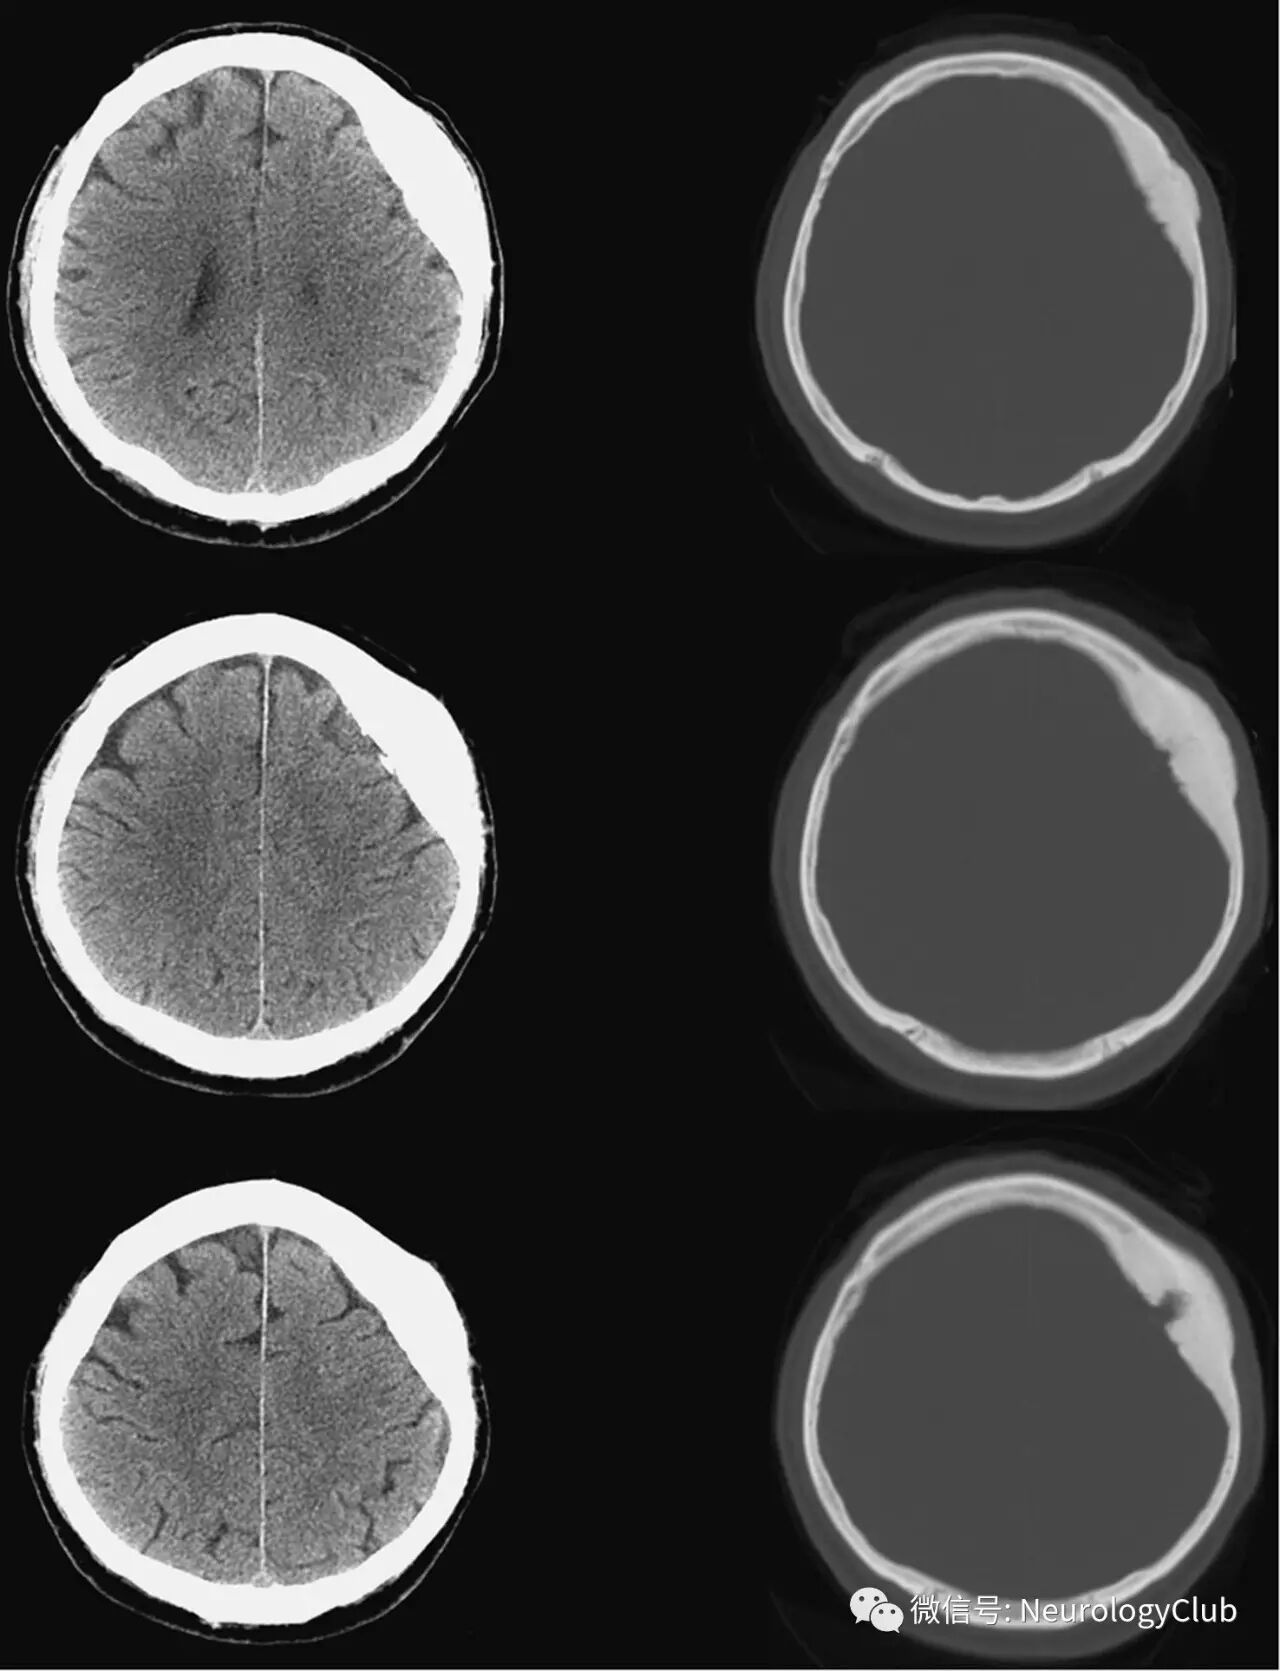

67岁男性,表现为进行性颅骨缺损6月。入院时,患者神经系统功能完好,触诊可摸及一骨性,无痛,无移动的肿块,约1.5cm,位于左侧额部凸面。头颅CT提示基于颅骨的病灶,左侧额顶部可见直径1.1cm的瘤巢,周围可见骨质硬化(图1)。瘤巢和其下硬脑膜可见轻度矿化。

(图1:CT提示基于颅骨的病灶,左侧额顶部可见直径1.1cm的瘤巢,周围可见骨质硬化)